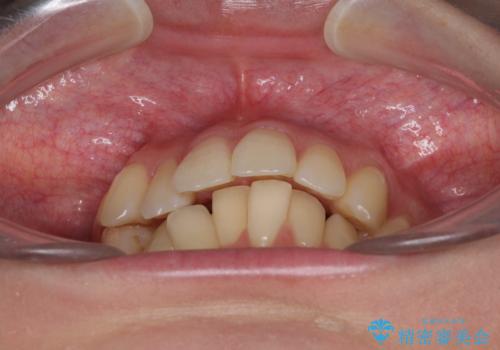

- 上の前歯、および下の歯列全体のでこぼこを気にして来院された患者様です。

インビザラインを用い、IPR(歯と歯の間を削る)と歯列全体を後方に移動させることで、歯並びを整えていくこととしました。

歯列全体を後方に移動させるため、下顎の親知らず2本を抜歯することとしました。